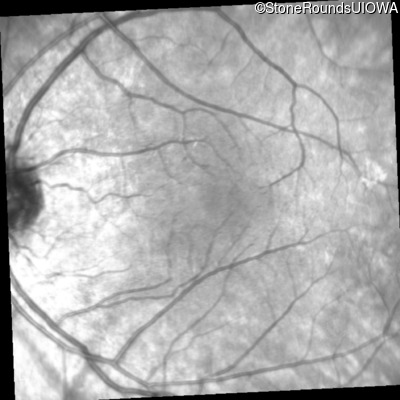

Infrared Fundus Photograph - Right - 20/25

Exemplar